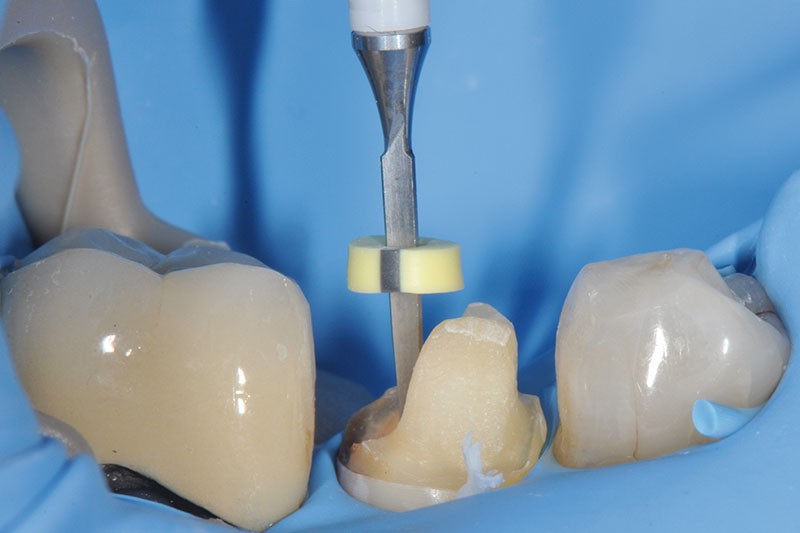

3, 4, 5. La restauration est déposée, les tissus carieux éliminés et la cavité d’accès aménagée avant la réalisation du traitement endodontique. La radiographie postopératoire permet de visualiser l’obturation du canal latéral en regard de la LIPOE.